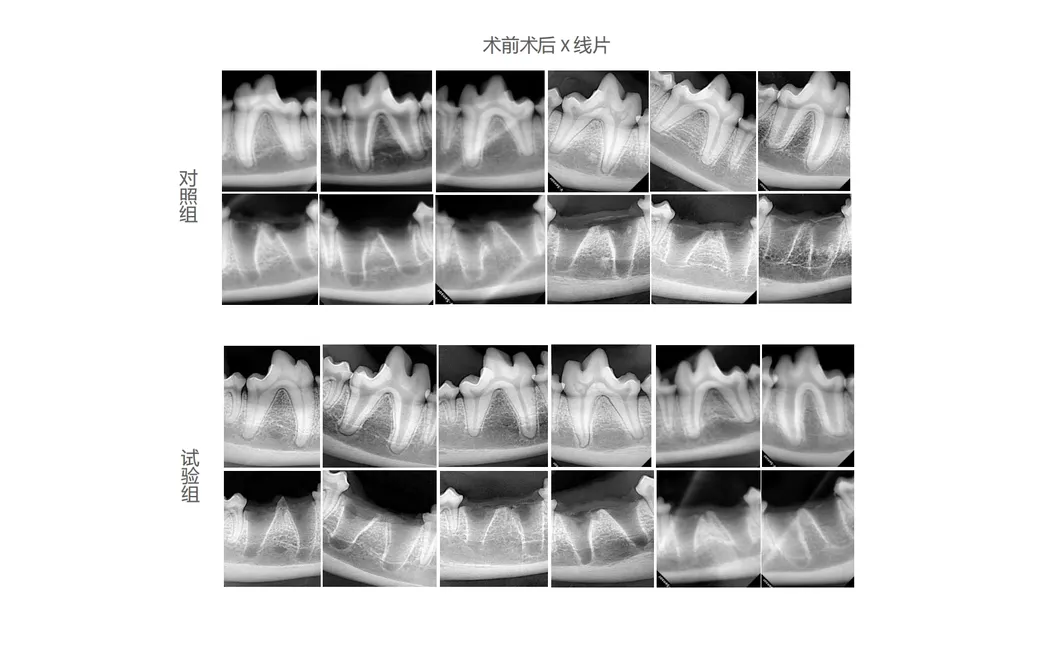

In this groundbreaking study, dogs were meticulously chosen to explore the effectiveness of revolutionary dental tools. The control group utilized traditional manual devices, while the treatment group utilized the advanced Pneumatic Dental Elevator Kit. Researchers documented physiological parameters, intraoperative complications, extraction duration, and socket damage. Sophisticated statistical analysis confirmed the superior performance of these advanced tools.

Experimental Result 1

Data Analysis